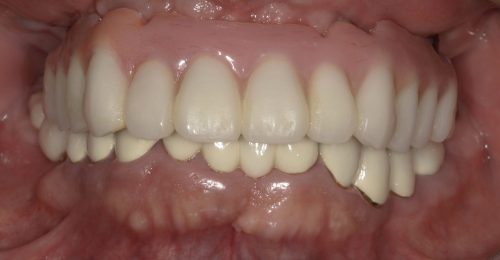

• オールオン4(上顎5本下顎4本)

術前

術後

年齢・性別 63歳・男性

治療期間 5ヶ月、通院回数18回

治療費用 5,720,880円(税込)

治療内容 歯周病により歯が動揺し噛めない状態。仕事に差し支えないように話しやすく、口元も綺麗にしたい。しっかり噛めるようにしたい。